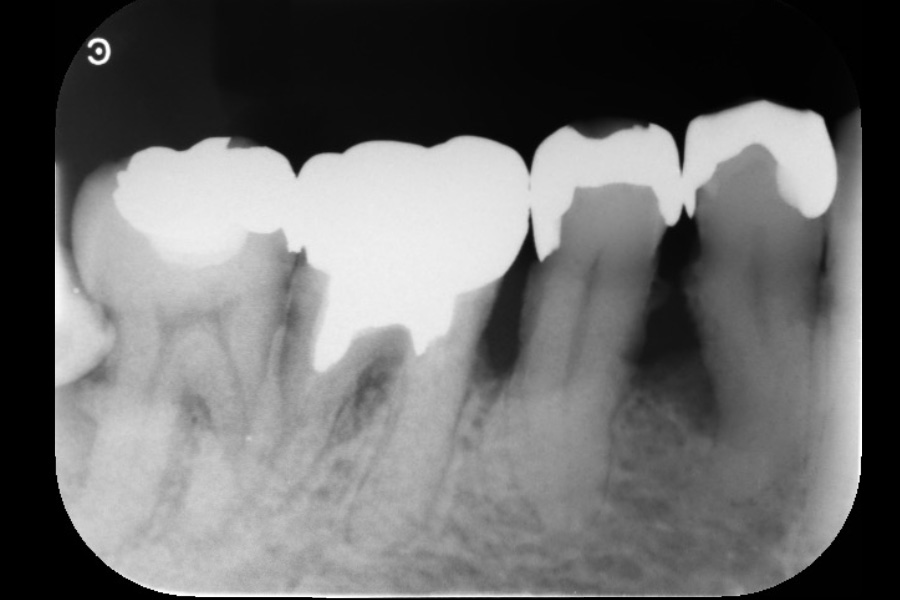

右下奥歯の歯ぐきから出血する

【歯周組織再生療法】

- 担当医

- 清水 宏康先生

- 主訴

- 右下奥歯の歯ぐきから出血する

- 期間

- 再生療法から再評価まで6か月

- 費用

- ¥220,000(税込)

- 治療内容

- 右下6遠心に垂直性骨吸収が認められたためエムドゲインと骨補填材を用いて歯周組織再生療法を行った

- 治療に伴うリスク

- 歯肉退縮、知覚過敏